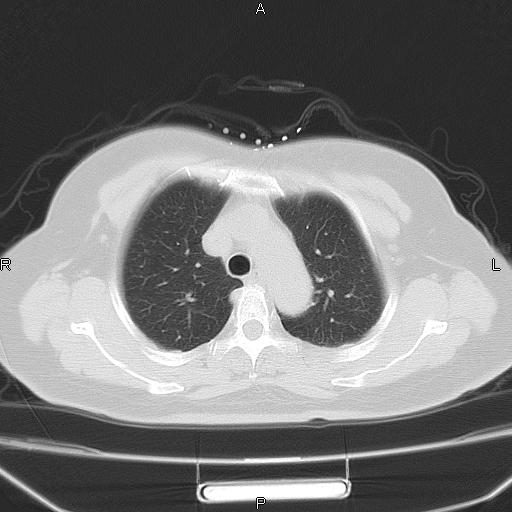

胸腺瘤

女、63Y 双眼睑下垂,早轻晚重。 胸腺瘤???

结果胸腺瘤